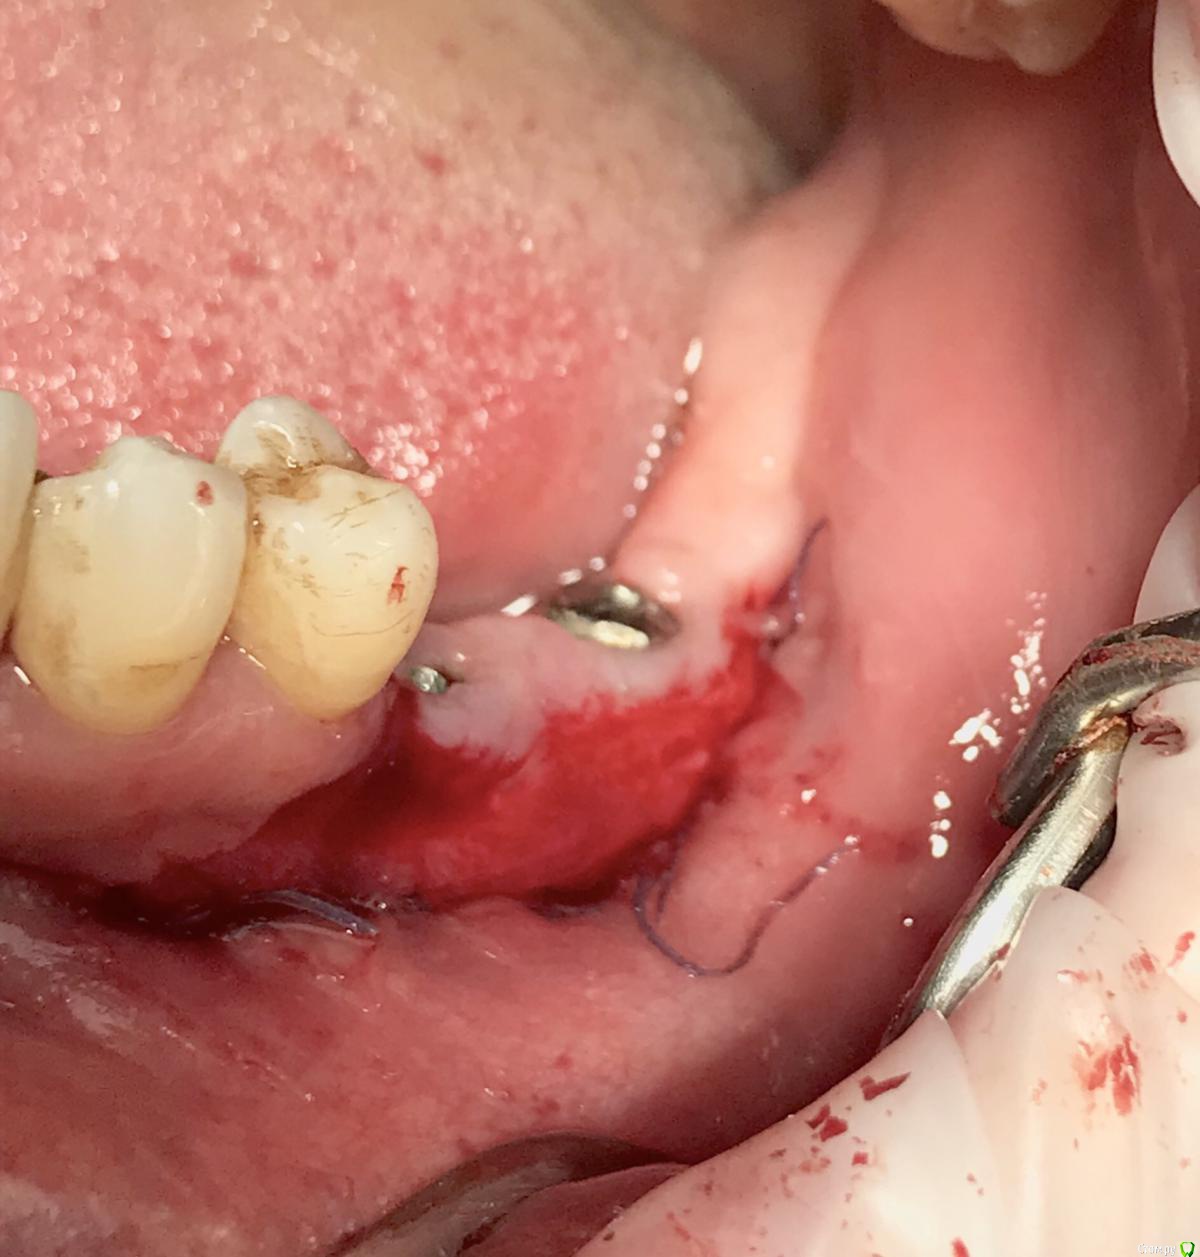

колесников Опубликовано 6 марта, 2019 Автор Поделиться Опубликовано 6 марта, 2019 Продолжение. За прошедшее время произведён асл,замена формирователей на 6ки. Периотест (-6) Ссылка на комментарий